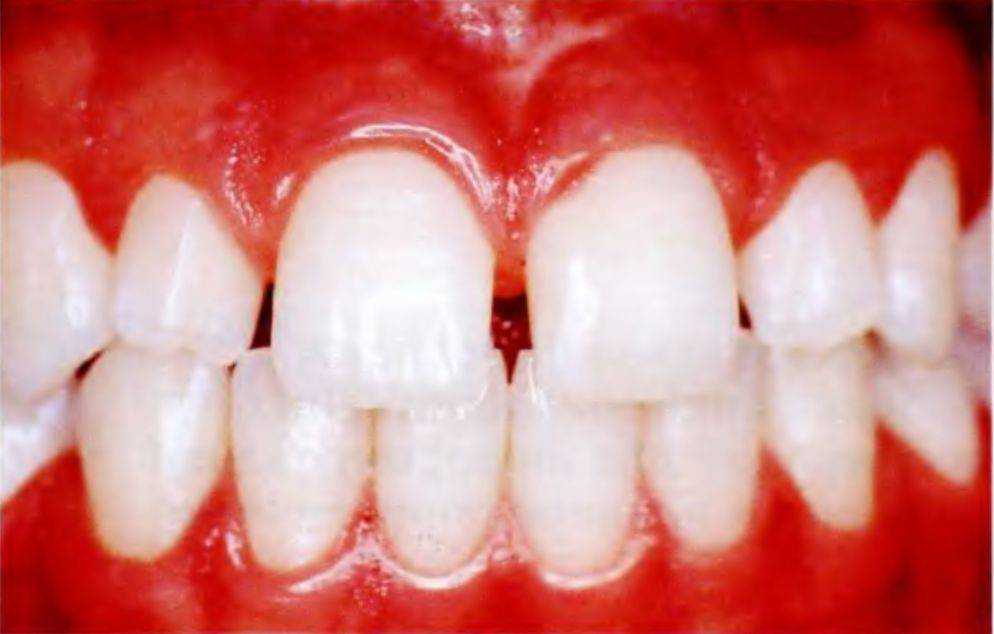

Мать 14-летней девочки обратилась в стоматологическую клинику после завершения ее ортодонтического лечения. Основное пожелание касалось устранения пространств между передними зубами верхней челюсти (рис. с 6-12с по 6-12е). Ортодонт опре-

Рис. 6-12с. Портретная фотография 14-летней пациентки

делил, что верхние зубы слишком узкие, поэтому устранение этих пространств ортодонтическими методами будет невозможно, и направил пациентку для проведения реставрационного лечения.

Стоматологическое обследование подтвердило мнение ортодонта. Межзубные пространства в переднем отделе верхней челюсти были слишком широкими, боковые резцы повернуты вокруг своей оси. Мать девочки предпочла адгезивные реставрации для максимального сохранения тканей зубов.